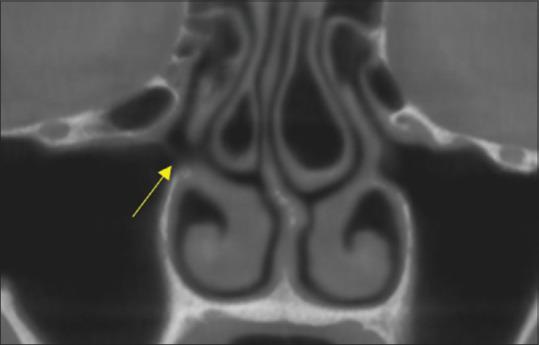

鼻窦开口复合体的解剖变异及其与上颌窦口通畅性的关系:锥形束计算机断层扫描的回顾性评估及其对鼻窦提升的影响。

Anatomic variations of the osteomeatal complex and its relationship to patency of the maxillary ostium: A retrospective evaluation of cone-beam computed tomography and its implications for sinus augmentation.

The aim of this study is to determine the incidence of obliterated osteomeatal complex (OMC) due to the presence of anatomic variants.

In this retrospective study, a total of 71 patients, 34 males and 37 females, aged 35-65 years were included in the study. Cone beam computed tomography (CBCT) scans of patients were assessed to identify the status of the OMC in the presence of anatomic variants and their incidence was recorded. The radiological assessment of the anatomical variants was made by viewing the coronal sections of the scans. The variants observed were deviated nasal septum, uncinate process), agger nasi, Haller cells, middle turbinate variants, enlarged bulla, accessory ostium, and maxillary sinus abnormalities). Ostium patency was evaluated in the coronal section of each sinus and classified as "patent" or "obstructed." The most common variants observed were then correlated with the patency of the ostium.

In the present study, the incidence of an obliterated OMC due to the presence of anatomic variants was 73.2%. The four most common variants associated with the possibility of an obliterated OMC were the deviated nasal septum (76.2%), middle turbinate (86.4%), enlarged bulla (77.8%), and sinus cavity variants (80.0%). A statistically significant association was noted between middle turbinate variants and Haller cells and the patency of the OMC.

Thorough pretreatment CBCT evaluation should be performed to assess the presence of anatomic variants and thereby, the patency of the ostium before sinus floor elevation procedures. The pre and postsurgical treatment plans and regimes can be modified according to anticipated postsurgical sequelae, thereby avoiding postsurgical complications and enhancing the success of the graft procedure.